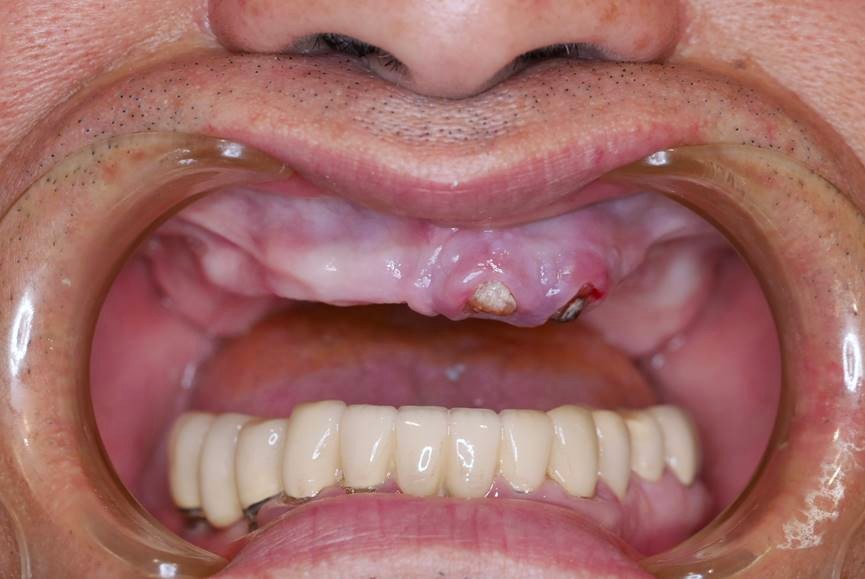

全口重建是我們的專長,針對全口缺牙或是全口鑲牙,需要全面整理,我們有一整套完整的診療模式。

這是因為植牙全口重建不僅是植牙而已,而是牽涉顳顎關節神經及咬肌,訓練咬合排利假牙位置,需要有經驗專業的假牙醫師,做全面綜合的考量,按步就班、細心每個步驟,才能完成令人滿意的植牙醫療成果,我們日出全植牙累積多年醫院全口重建的經驗。

從建的方式有很多種,有固定的、有活動的,有種4顆、有種6~16顆。假牙有些有牙齦有些沒有,有分段式有全口。

植牙假牙泡在口水裡,每天使用是每次承受咬合力挑戰,加上口內細菌繁多,每個人體質不同,牙肉骨頭萎縮,所以全口植牙的長期照護維修尤為重要。不僅在計畫之初就要想到日後可能產生的問題、解決方法、維修的便利性。